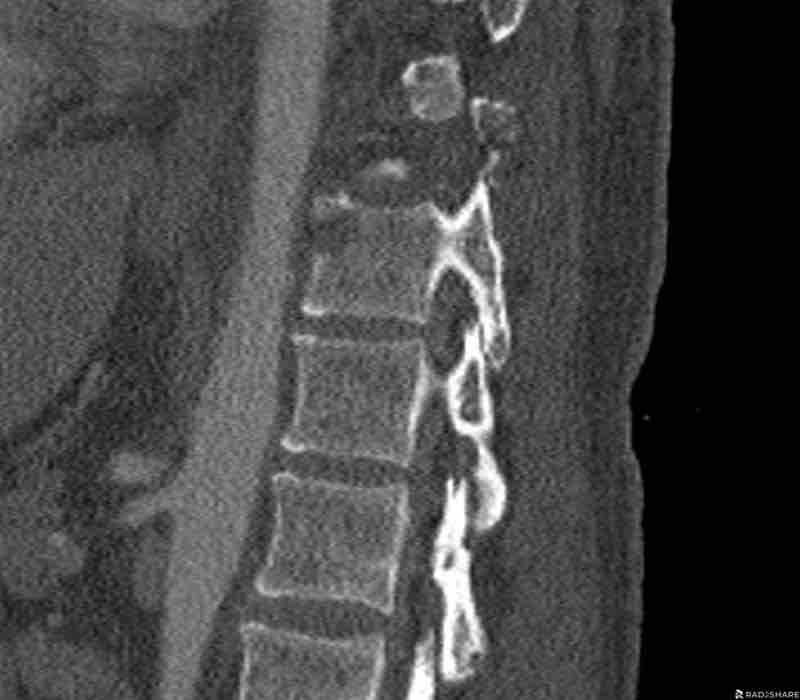

Scroll through the images.

What is the highest AO-type of injury?

Any additional findings?

Findings

- Subtle widening of the interspinous distance (white circle)

- Small avulsion fracture spinous process (yellow arrow)

- Compression fracture with involvement of one endplate and posterior wall (1+2 points)

Conclusion

Injury type B2 + A3